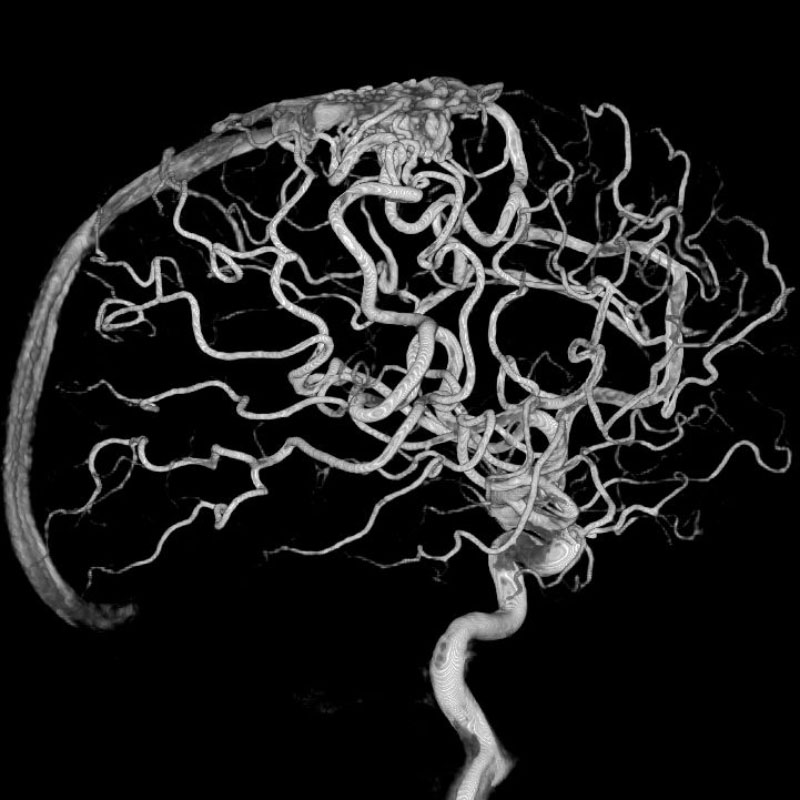

画像